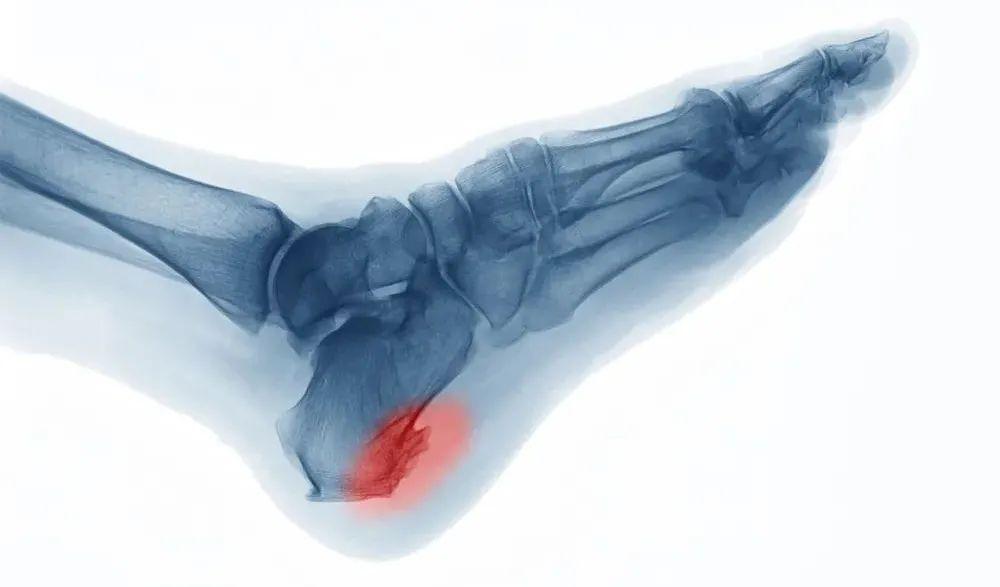

2、 跟骨骨刺

足底筋膜在跟骨附着部位形成的锥状骨质称为骨刺,多与跟腱和跖筋膜方向一致,是老年人骨与关节发生退行性变的生理特征性表现,但有跟骨骨刺的患者,并不一定造成足底筋膜炎。

当骨刺长期存在,且跟骨长期负重或负重过大,造成局部充血和无菌性炎症时,刺激病变部神经,则引发足跟部疼痛症状。